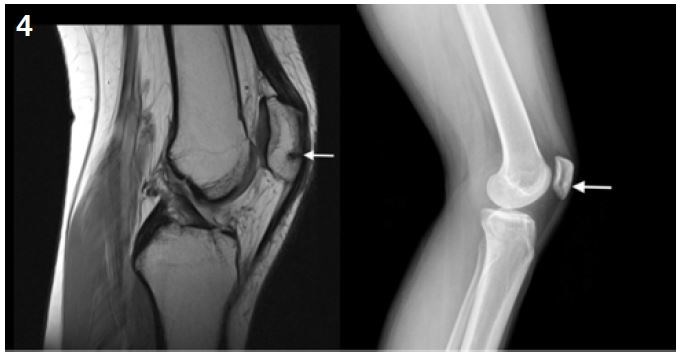

Patella stress fracture: 1% of all BSF20. It mainly occurs in young female athletes (3 women to 2 men). Risk factors are patellar malalignment and lateral tracking dysfunction21.

Clinically, patients present with anterior knee pain associated with sport, sometimes with an associated joint effusion. Patellar palpation is painful12.

XR sensitivity is low.  MRI is more specific and enables an accurate diagnosis and can identify any associated lesions (such as a cartilage lesion).

Treatment is not always surgical. Incomplete and non-displaced fractures may benefit from a 6-week period of immobilization without weight bearing. But if the fracture is displaced and in high demand patients, surgical fixation can be performed with two non-absorbable braided wire devices secured by a button at each end (such as Syndedsmosis TightRope or Invisknot ankle syndesmosis) with efficient stabilization while avoiding the disadvantages of metallic devices that will have to be removed. Return to sports activity can be expected at six months post-op6 (Figures 4 and 5).

Figure 4: Transversal patellar fracture: MRI and radiological image.